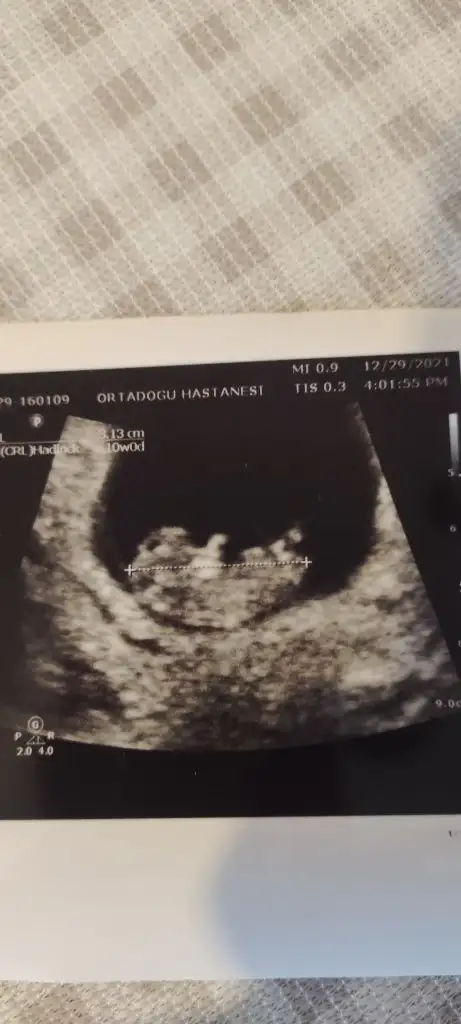

Erkek gibi sanki emin olamadımMerhaba 12+2 di burda bende tahmin alabilirmiyim rica etsem

Şimdilik kız yönünde ama en iyi 11 12 13 haftalar olmalı